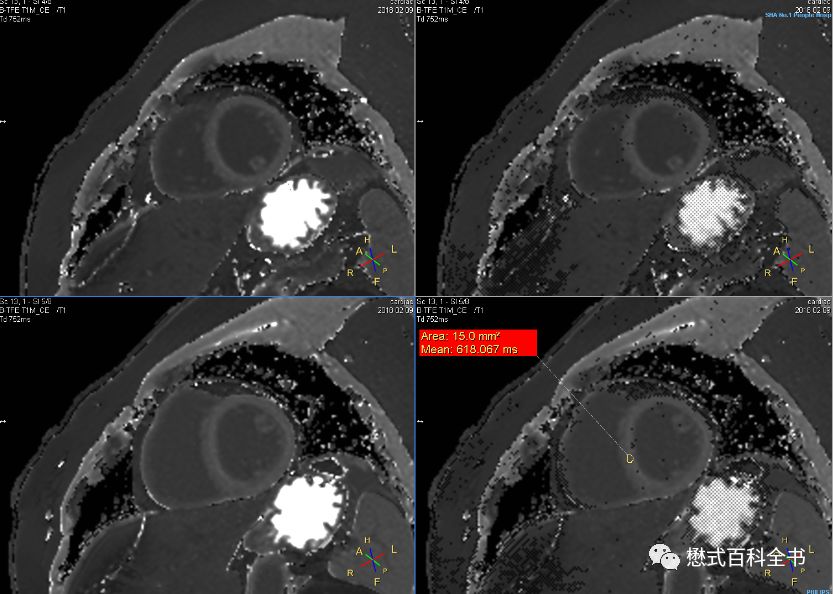

图7:测量T2值

T2 mapping相对来说不需要后处理,扫描完了可以得到T2定量图,通过在图上划ROI可以测量其所感兴趣区域的T2值。

T2 mapping就是测量策划的T2值的一种磁共振定量技术,通过测量成像FOV内各个基本的体元(体素)的T2值,然后重建得到一副折射策划T2值分布的T2值图(T2 mapping)。

一般来讲T2 mapping在心脏磁共振中主要用于鉴别心肌缺血、炎症、脉管炎及相关的心肌水肿。